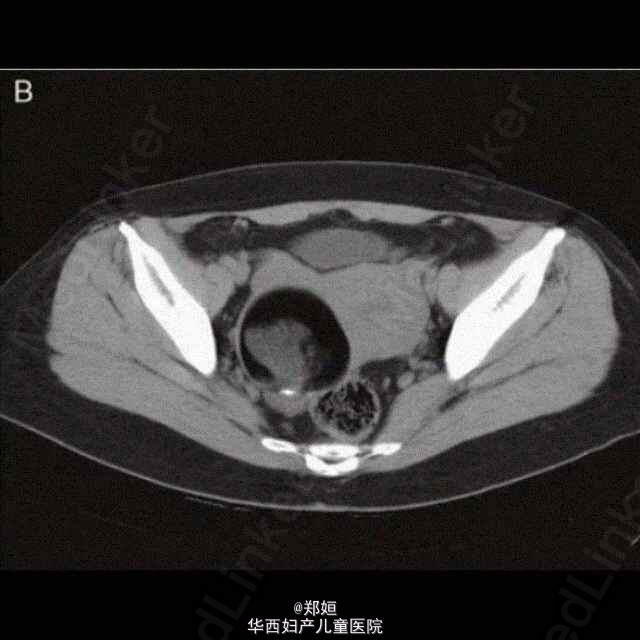

46岁女性,G2P2,腹部可触及包块。 通过超声可见2周内肿块直径从4.6cm长到了8.1cm。 CT示子宫体右侧有一肿瘤伴有脂肪组织。 初步诊断为畸胎瘤,行剖腹探查术。 术中可见肿瘤位于子宫底,完整未破裂,双侧卵巢肉眼观正常。